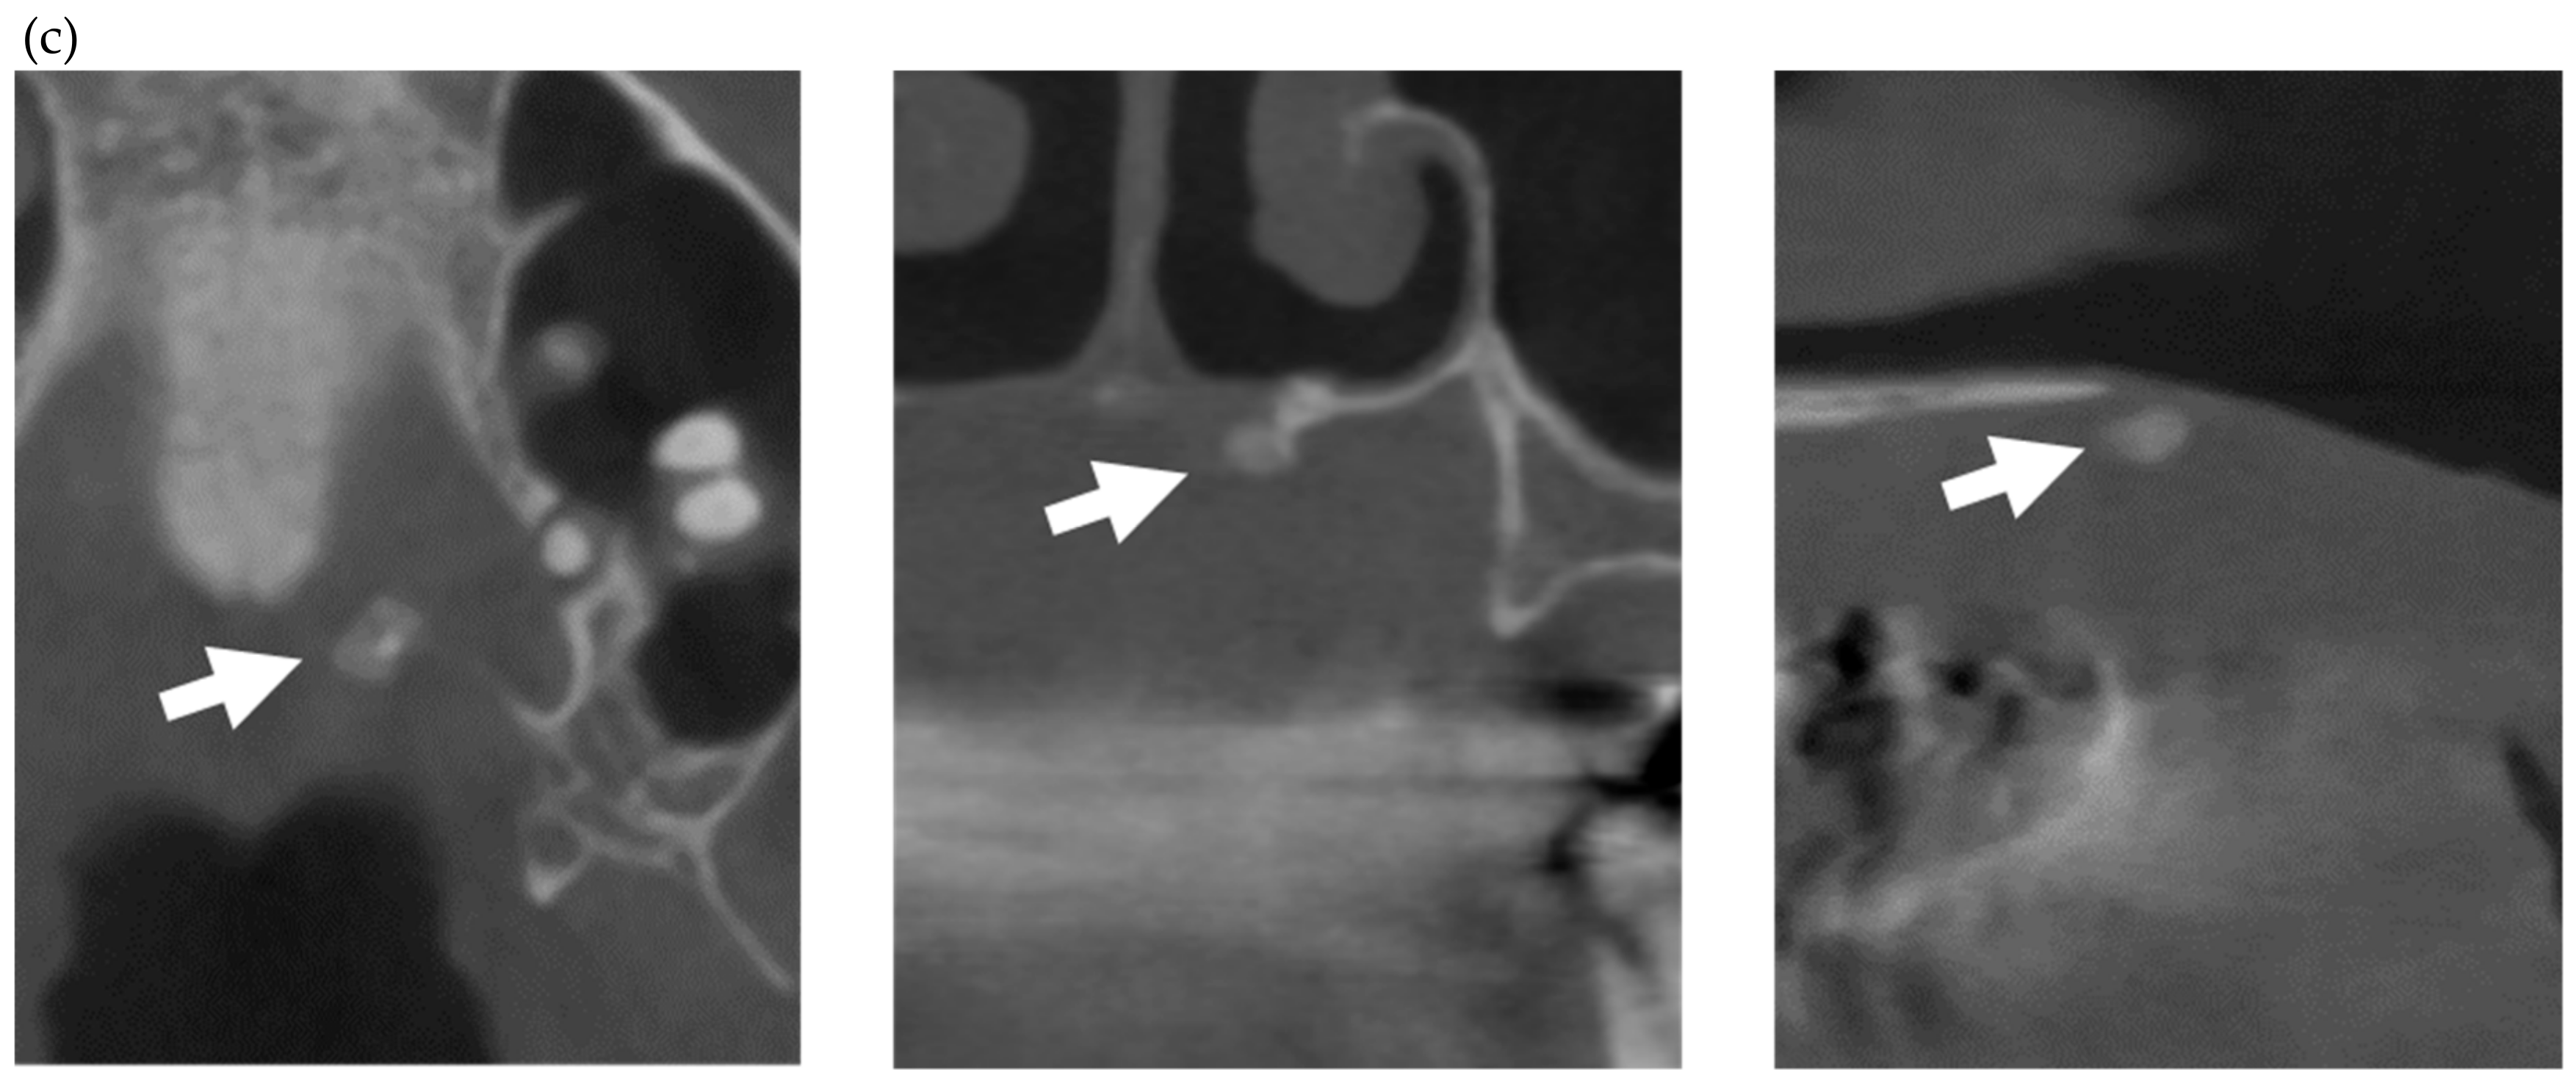

- Matsuda, S.; Memida, T.; Mizuno, N.; Ogawa, I.; Ouhara, K.; Kajiya, M.; Fujita, T.; Sugiyama, E.; Kurihara, H. Reparative bone-like tissue formation in the tooth of a systemic sclerosis patient. Int. Endod. J. 2018, 51, 1059–1066. [Google Scholar] [CrossRef] [PubMed]

- Arroyo-Bote, S.; Bucchi, C.; Manzanares, M.C.; Céspedes, M.C.M. External Cervical Resorption: A New Oral Manifestation of Systemic Sclerosis. J. Endod. 2017, 43, 1740–1743. [Google Scholar] [CrossRef] [PubMed]